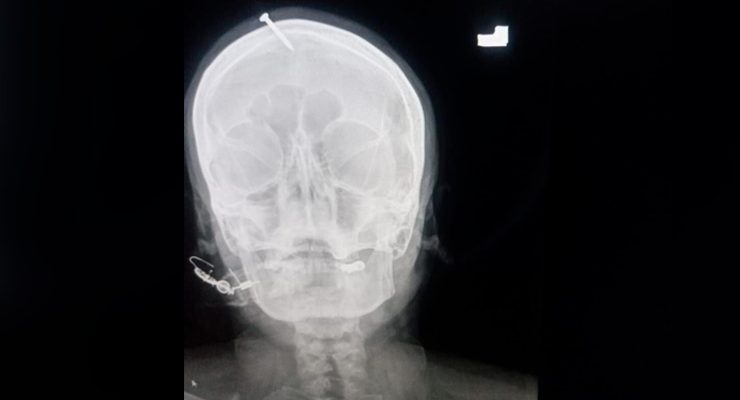

في باكستان سيدة تدخل مسمار في جمجمتها لتنجب ولد

صدم الأطباء في مستشفى ليدي ريدينج في بيشاور في باكستان بالصدمة عندما فحصوا رأس امرأة حامل…